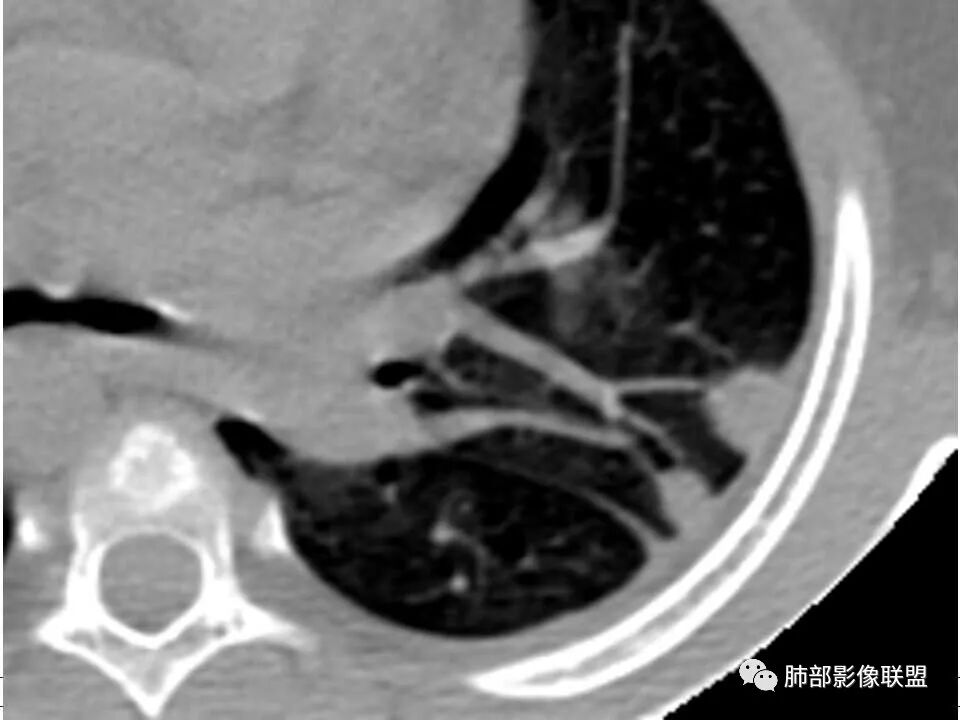

患者儿童,因右下肢疼痛伴肿胀14天就诊。病程中有发热及伴随症状。膝关节MRI提示右侧膝关节及右髌骨髁异常信号影,右膝髌上囊及关节腔内少量积液。胸部CT:双肺胸膜下多发结节影,部分结节空洞形成,且结节周围可见血管集束征。综合考虑血源性脓毒性肺栓塞、坏死性肺炎。右侧骨髓炎、血播性金葡菌肺炎,鉴别其他特殊感染及血管炎。

胸部ct:双肺多发空洞,结节,外带下叶为主,空洞内外光滑,有血管滋养征,综合病史及影像考虑脓毒性肺栓塞,结合病史,金葡可能性大。

小儿,急性起病,下肢疼痛,mr提示骨髓水肿,临床化验炎性指标高,考虑金葡菌骨髓炎,双肺多发结节,以血管支气管束及胸膜下分布为主,部分结节近端与血管相连,部分结节可见空腔,内壁光整,部分囊腔有张力,考虑骨髓炎并肺内血播感染,金葡?

1. 多发胸膜下外周结节、< 3 cm 的楔形影和滋养血管征 CT 表现;

4.经恰当的抗生素治疗,肺部浸润影吸收。滋养血管征为一支血管影连接肺部周边病灶,在 2/3 以上患者出现,可作为高度提示 SPE 的征象。